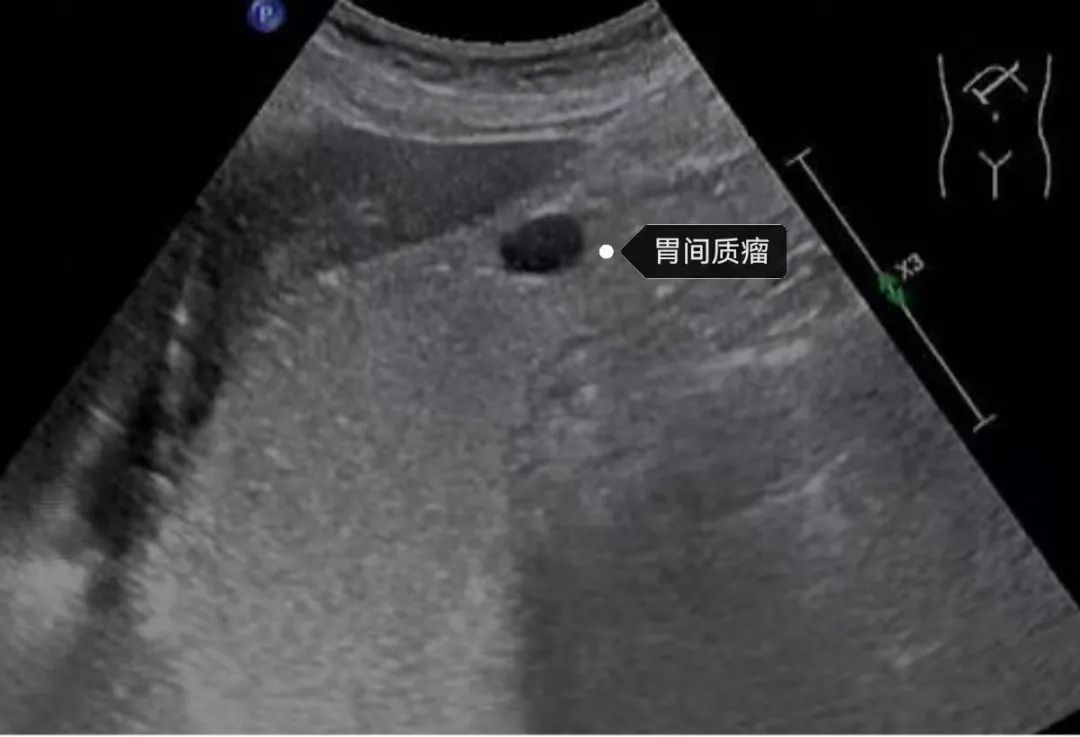

1.肿瘤性病变:如:胃息肉、平滑肌瘤、胃癌等。

典型病例分享